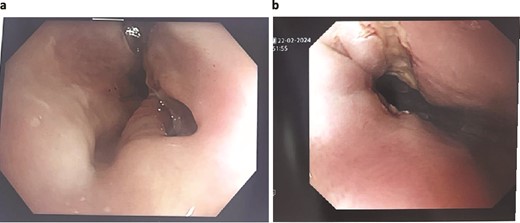

A 89-year-old male, diagnosed with Boerhaave syndrome and oesophageal perforation was transferred from one hospital to another on day 13 post-diagnosis. Initial diagnostic tests, including a gastrografin swallow, identified a defect in the distal left lateral wall of the oesophagus, measuring ˂1 cm with an extraluminal component of at least 5 cm (Fig. 2a).

Patient Two: (a) Before VACStent insertion, showing the oesophageal defect. (b) After VACStent treatment, demonstrating successful defect closure.

On day 14 post-diagnosis, the patient underwent an oesophago-gastro-duodenoscopy (OGD) and VACStent insertion, which was kept in place for 6 days. A CT thorax on day 16 post-diagnosis confirmed proper placement of the VACStent with no ongoing leak (Fig. 2b). The patient underwent ultrasound-guided drainage for a left pleural effusion on day 17 post-diagnosis and remained nil by mouth. Subsequent imaging showed a decrease in the oesophageal defect size, and by day 22 post-diagnosis, the patient was advised to start a soft moist diet, which was well tolerated.